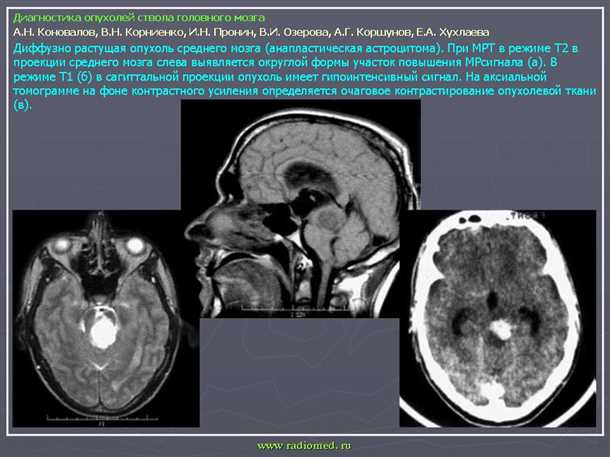

Роль Магнитно-резонансной томографии (МРТ) в выявлении воспалительных и пораженных сосудистых образований мозга

Преимуществами МРТ являются высокая разрешающая способность и возможность получать изображения мягких тканей с высокой контрастностью. Этот метод позволяет обнаруживать изменения в структуре и функции сосудов мозга, такие как воспалительные процессы, нарушения кровообращения или аномалии развития.

Магнитно-резонансная томография (МРТ) проводится с использованием магнитного поля и радиоволн. Наблюдаемое в результате исследования изображение головного мозга оказывается под воздействием различных физических параметров, что позволяет определять отличительные особенности сосудистых образований и тканей мозга, а также выявлять патологические изменения.

В МРТ можно использовать конtrastные вещества для повышения контрастности изображения. Это позволяет выявить наличие опухолей, кровотечений, воспалительных очагов и других изменений в сосудах головного мозга. Благодаря применению МРТ, врачи имеют возможность точно определить расположение и размер сосудистых аномалий, а также выяснить их влияние на работу и состояние мозга.

Таким образом, Магнитно-резонансная томография (МРТ) является эффективным методом диагностики поражений сосудов головного мозга. Ее преимуществами являются высокая точность, возможность получения подробного изображения и выявления изменений в структуре и функции сосудов мозга. МРТ с использованием контрастных веществ позволяет выявить наличие воспалительных, пораженных или измененных сосудистых образований, что помогает врачам выбрать оптимальный метод лечения и контролировать эффективность проводимой терапии.